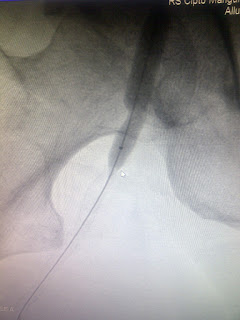

Penanganan Total Oklusi Arteri Iliaka Kiri

Oklusi total arteri iliaka kiri adalah suatu kondisi yang mengancam kelangsungan hidup tungkai.

ditampilkan satu kasus total oklusi arteri ilaka kiri yang berhasil dilakukan balloning

Penderita ini penderita kritikal limb iskemia dan direncanakan dilakukan bypass sebelumnya. sebagaimana kita ketahui bahwa tindakan bypass adalah tindakan yang invasif dan dengan luka operasi yang besar.

Pada pasien ini rencana operasi bypass nya dibatalkan karena keluhan dan tanda tanda iskemia tungkainya segera menghilang sesudah dilakukan intervensi